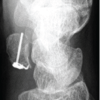

The patient’s wrist was immobilized in a below-elbow plaster slab for 4 weeks and then transitioned to a splint/brace. Early finger motion was encouraged from day 1. Gentle wrist mobilization was started at 7 weeks after removal of the K-wires, followed by progressive ROM and grip strengthening thereafter. The patient resumed his job as a driver at 3 months post-operatively. At 12 months after the surgery, the patient reported minimal discomfort with activities of daily living, no night pain, and no sensory complaints. He was able to bear weight on his wrist and perform his job as a driver without limitations. The surgical wound was well healed and there was no mass or localized warmth. Final ranges of motion were good (Fig. 3), with 50° dorsiflexion, 40° palmar flexion, 90° pronation, and 90° supination.

Figure 3: Post-operative clinical images with wrist range of motion (left); antero-posterior wrist radiograph taken at 12 months post-operatively (right).

Grip strength as a percentage of that of the healthy side was 80–85%, Mayo Wrist Score was 85 (Good), and disabilities of the arm, shoulder, and hand score was 8.3. VAS score was 1–2/10, but only during exertion. Surveillance imaging at 12 months follow-up showed maintained carpal alignment and good graft incorporation, with some relatively lucent areas in the middle of the iliac crest graft (Fig. 3). A Fluorodeoxyglucose positron emission tomography-computed tomography was done at this stage to rule out local recurrence, and it turned out to be negative for the same and also for distant metastasis.